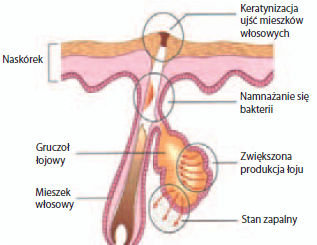

Trądzik pospolity to najczęstsza choroba gruczołów łojowych, związana przede wszystkim z nadprodukcją łoju.

Trądzik pospolity to najczęstsza choroba gruczołów łojowych, związana przede wszystkim z nadprodukcją łoju.